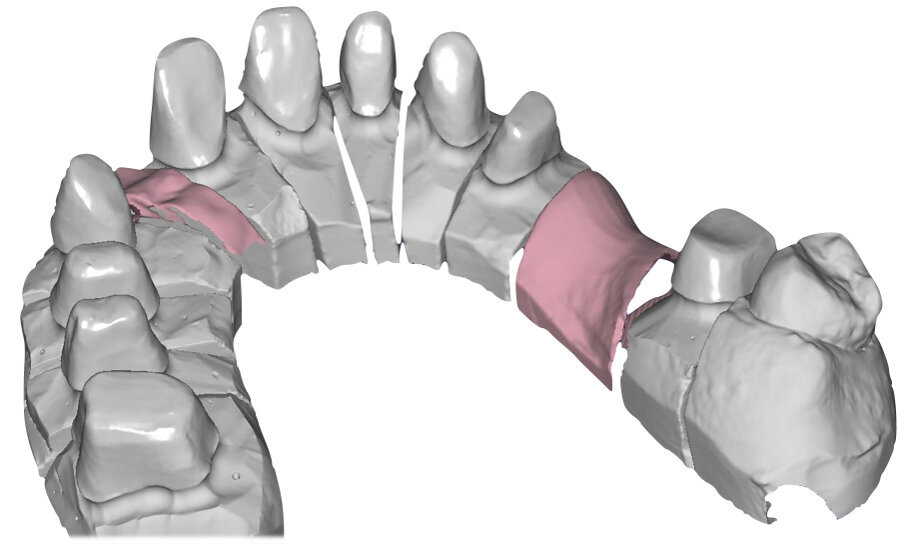

Si esegue perciò cefalometria (Fig. 8) su radiografia latero-laterale (Fig. 9) e axiografia dei movimenti limite (Cadiax Compact, Gamma Dental) (Fig. 10) per la programmazione di un articolatore a valori medi (Artex TR, AmmanGirrbach) e montaggio dei modelli con arco faciale, che confortano nella produzione di un primo provvisorio prelimatura con rialzo arbitrario della VDO di 5 mm sull’asta incisale e miglioramento di OB e OJ, a scopo pre-terapeutico interlocutorio e di immediata risoluzione estetica. Conclusa la necessaria terapia causale e restaurativa viene eseguita la scansione intraorale delle arcate (TRIOS 3 Pod, 3Shape) (Figg. 11-14) e del rapporto articolare con cera di RP (Fig. 15). La scansione è stampata (VisiJet RWT, 3D Systems) con monconi sfilabili tramite stampante 3D (ProJet MJP 2500 Plus, Selltek) (Figg. 16-20), i modelli derivanti sono zoccolati e montati con cere di RP e arco faciale su articolatore a valori individuali (Reference SL, Gamma Dental). La programmazione dell’articolatore derivante dalla registrazione axiografica è ora eseguita come da indicazioni del software (Gamma Dental software, sia per l’uso degli inserti condilari ed incisali, sia per la definizione degli angoli di SCI e di Bennet (Fig. 21). Lo spazio protesico risultante a una VDO adeguata alla riabilitazione dei denti anteriori vitali, con anatomia non ulteriormente modificabile, è insufficiente per uno stabile ripristino dei rapporti occlusali, specie nei tragitti funzionali. Si decide perciò di impiegare due inserti rossi di programmazione di protrusiva (+2 mm) per riposizionare la mandibola in TRP (Figg. 22, 23).

Ciò consente un miglioramento dei rapporti interarcata, un guadagno di spazio protesico in regioni premolari e molari, ed il mantenimento di uno spazio protesico conforme ad una corretta anatomia per i denti vitali da 1.3 a 2.3. Al paziente viene pertanto aggiornato il piano di trattamento e proposta la riabilitazione in TRP, con la previsione di overlays all’arcata inferiore per costruzione del nuovo piano occlusale. In posizione terapeutica sono modellati i coni delle centriche attive sui monconi sfilabili all’arcata inferiore, per la successiva individuazione al CAD con modulo articolatore del piano occlusale studiato. Questo rapporto articolare in TRP è ora scansito con scanner da laboratorio Xanos Evo Scan Compact (Fig. 24).

I modelli sono così importati in corretta posizione spaziale tramite il modulo exocad Virtual Articulator (Fig. 25). Non avendo a disposizione nel CAD l’analogo virtuale dell’articolatore Reference SL, viene impostato il sistema virtuale SAM, che usa lo stesso piano di riferimento axio-orbitale e geometria sovrapponibile al Reference SL. Per la programmazione virtuale dei parametri funzionali dell’articolatore si riesegue l’output dall’axiografia elettronica con Gamma Dental per SAM (Fig. 26). Si procede perciò ora con la modellazione CAD della ceratura mantenendo il riferimento dato dal piano occlusale individuato dai coni di centrica scansiti con l’articolatore (Fig. 27). L’articolatore virtuale consente una prima verifica dei rapporti occlusali tra gli elementi e un abbozzo di funzionalizzazione delle cuspidi con strumenti virtuali dinamici, che permette di arrivare ad un CAD design vicino alla morfologia ricercata (Figg. 28-33). Il modellato è ora fresato in cera Yeti Dental al CAM con fresatore VHF Cam5-S1 ed i denti in cera, tutti singolarmente sfilabili, sono posizionati sui modelli eseguiti con stampa 3D.